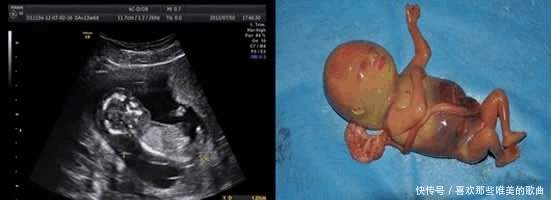

目前国内新生儿缺陷率高达5%,每年都有100万先天性残疾儿童出生。而导致孩子畸形的原因其实是有很多的,比如孕妇不注意饮食,高龄生育或者夫妻双方存在遗传因素。

胎儿畸形高发的阶段是在孕妈怀孕后的前三个月,在这个时期胎儿受到外界刺激又或者是其他影响,将会对他们造成无法逆转的伤害。

1、3-8周

这个时期的胎儿主要处于器官分化期,对外界非常敏感,一旦不注意很容易出现器官异常现象。据不完全数据统计,大多数严重的畸形以及胚胎自然流产都发生在这个阶段。

2、8-12周

这个时候胚胎已经成为胎儿了,胎儿慢慢出现了手和脚,等到了10周之后,宝宝的各器官已经出现。12周时,胎儿的生殖器也开始发育,眼睛慢慢成形。等到了9-12周,胎宝宝对外界致畸因素的敏感慢慢降低,但比起孕中期以及孕晚期来说,还是不能忽视。